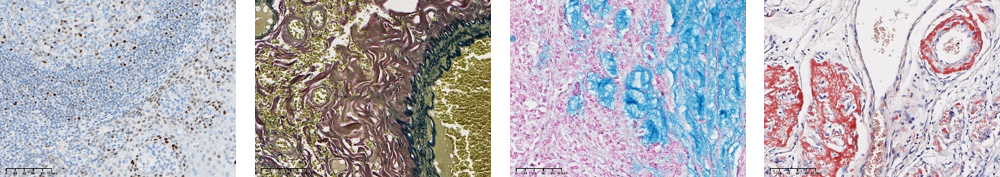

近日,熙寧生物|精翰生物參加中國(guó)非公立醫(yī)療機(jī)構(gòu)協(xié)會(huì)病理學(xué)專業(yè)委員會(huì)和國(guó)家病理質(zhì)控中心(PQCC)非公組聯(lián)合組織的特殊染色室間質(zhì)評(píng)活動(dòng),檢測(cè)指標(biāo)包括MSH2、MSH6、MLH1、PMS2、ER、PR、HER2、KI67、Claudin18.2、CD20、Bcl-2、Bcl-6、C-MYC、彈力纖維染色、粘液染色(AB[Ph2.5]法)、淀粉樣蛋白染色(剛果紅法),以上16項(xiàng)檢測(cè)指標(biāo)熙寧生物|精翰生物組織病理平臺(tái)均高分通過(guò),榮獲合格證書(shū)。

彈力纖維染色

粘液染色

剛果紅染色